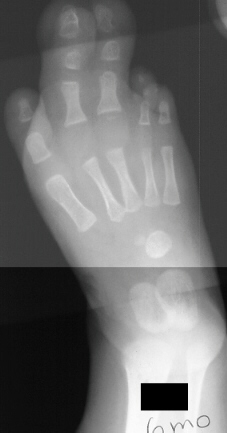

At age 12 months a girl presents severe overgrowth of the

foot. She was the product of a normal pregnancy and delivery and

is otherwise completely healthy. The parents main complaint is

that she can not be fitted with shoes. She had an amputation (image

1 & 2) of the 2nd and 3rd toes at the level of the mid diaphysis,

proximal phalanx and extensor tendon release of the 2nd and 3rd

toes with excision of abnormal fibrofatty tissue of right foot,